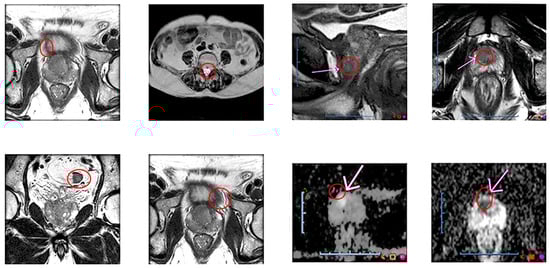

The data preparation pipeline, illustrated in Figure 1, consists of several critical steps to process and organize the MRI images efficiently. Initially, MRI images are stacked layer by layer to create comprehensive 3D representations, preserving the spatial information essential for accurate analysis. To enhance the dataset’s robustness, data augmentation techniques such as rotation, flipping, and scaling are applied, diversifying the dataset while maintaining its integrity.

Figure 1. Data preparation pipeline for false-negative lesions with multiple parameters.